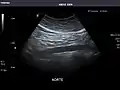

Aorta

Aorta: Visualized portions normal in caliber, 16 x 15 mm.